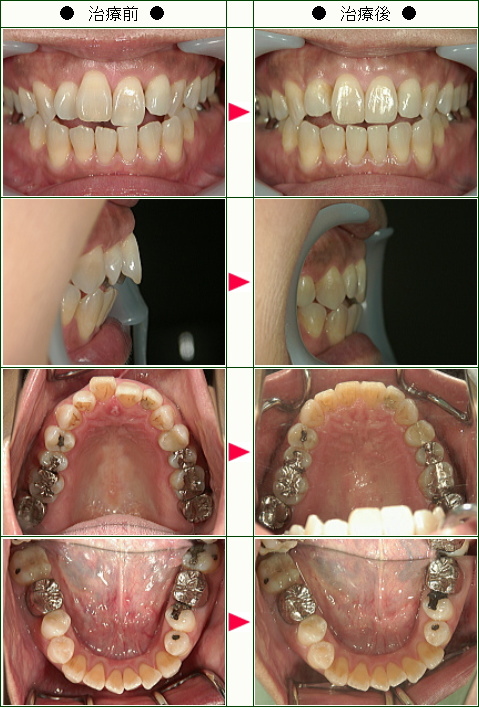

「周りの友達には「この歳になってなんで?」と驚かれました」M・M様 61歳 女性

元々歯並びは良いとは言えませんでしたが、悪いなりに左右対称で子供の時は笑うと八重歯がかわいいなどと言われ、全く気にしてはいませんでした。

しかし、60才頃から対称が崩れ、デコボコの全く不規則な並びが顕著になり、かわいい八重歯どころか鬼歯の様相を呈して来ました。

かかりつけの歯医者さんが、この傾向はますます進むと言った時、矯正を決意しました。

周りの友人達には「この年齢になってなんで?」と驚かれました。

近所で矯正歯科に複数話を聞きに行きましたが、治療法も期間も料金も全く異なり迷いました。

一番嫌だと思ったのは、どちらも真ん中から4番目の歯を上下左右計4本抜くと言われた事です。

そこで図書館から歯列矯正の本を借り読みました。

そこで南青山デンタルクリニックの青山先生の本と出会い、近年の抜かない矯正を知り、その治療方針、姿勢に心配もふっとび、ここなら安心と開始しました。

当時、骨粗しょう症の治療薬を飲んでおり抜歯の際のリスクの相談、初めてブラケットを装着した後起こった湿疹が金属アレルギーかとの動揺等、何かと心配事の多い私でしたが、青山先生のいつも落ち着いた誠実な物腰と説明に不安も消え、安心して治療を進める事ができました。

担当の歯科衛生士さんもていねいで、きちんとした仕事ぶりで、治療の折にはいつも痛みを気遣って進めてくれました。

歯垢や歯石も歯茎の中まで除去するのだと初めて知りました。

ブラケットやマウスピースの装着は、確かに初めは少し痛かったり、充分噛めなかったり、味覚でさえ楽しめなかったり、不敏でわずらわしいものです。

でも逆に、この体験で私は咀嚼というものが、いかに歯や歯並びや舌の複雑で精巧な連携の上に成り立っているか分かりました。

「おいしさ」は舌だけで感じるものではないのですね。

過ぎてしまえばあっという間です。

いっそ今は「部分」ではなく「全部」やっておけば良かったと思ったりさえします。